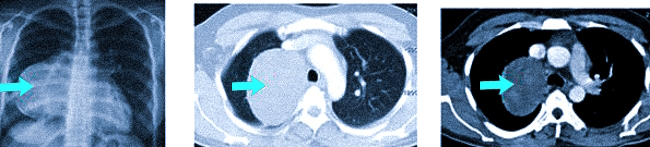

На рентгеновских снимках и КТ можно наблюдать объемное бронхогенное образование у новорожденного (стрелки указывают на патологию).

Данная патология иногда обнаруживается в утробе матери во время планового ультразвукового обследования или сразу после рождения. В данной ситуации, учитывая потенциальную угрозу для жизни, врачи настоятельно рекомендуют хирургическое вмешательство, особенно в постнатальный период, когда риск кровотечений, инфицирования и малигнизации высок. Удаление кисты является приоритетным.